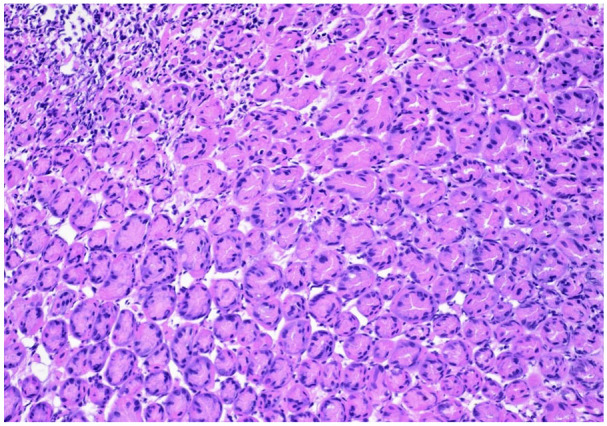

Oxyntic gland adenomas (OGAs) are benign gastric neoplasms composed of gland-forming epithelial cells with predominantly chief cell differentiation resembling oxyntic glands confined to the mucosa. If the tumor has submucosal invasion, it should be classified as gastric adenocarcinoma of fundic gland type. The OGAs can pose a diagnostic challenge, as they can resemble aggressive gastric neoplasms. There are no current guidelines on the management of OGA. Due to the relatively small size and low malignant potential, these lesions are typically managed endoscopically. In this case, we are reporting a 22-year-old woman who was diagnosed with OGA during evaluation of iron deficiency anemia and underwent successful endoscopic resection.